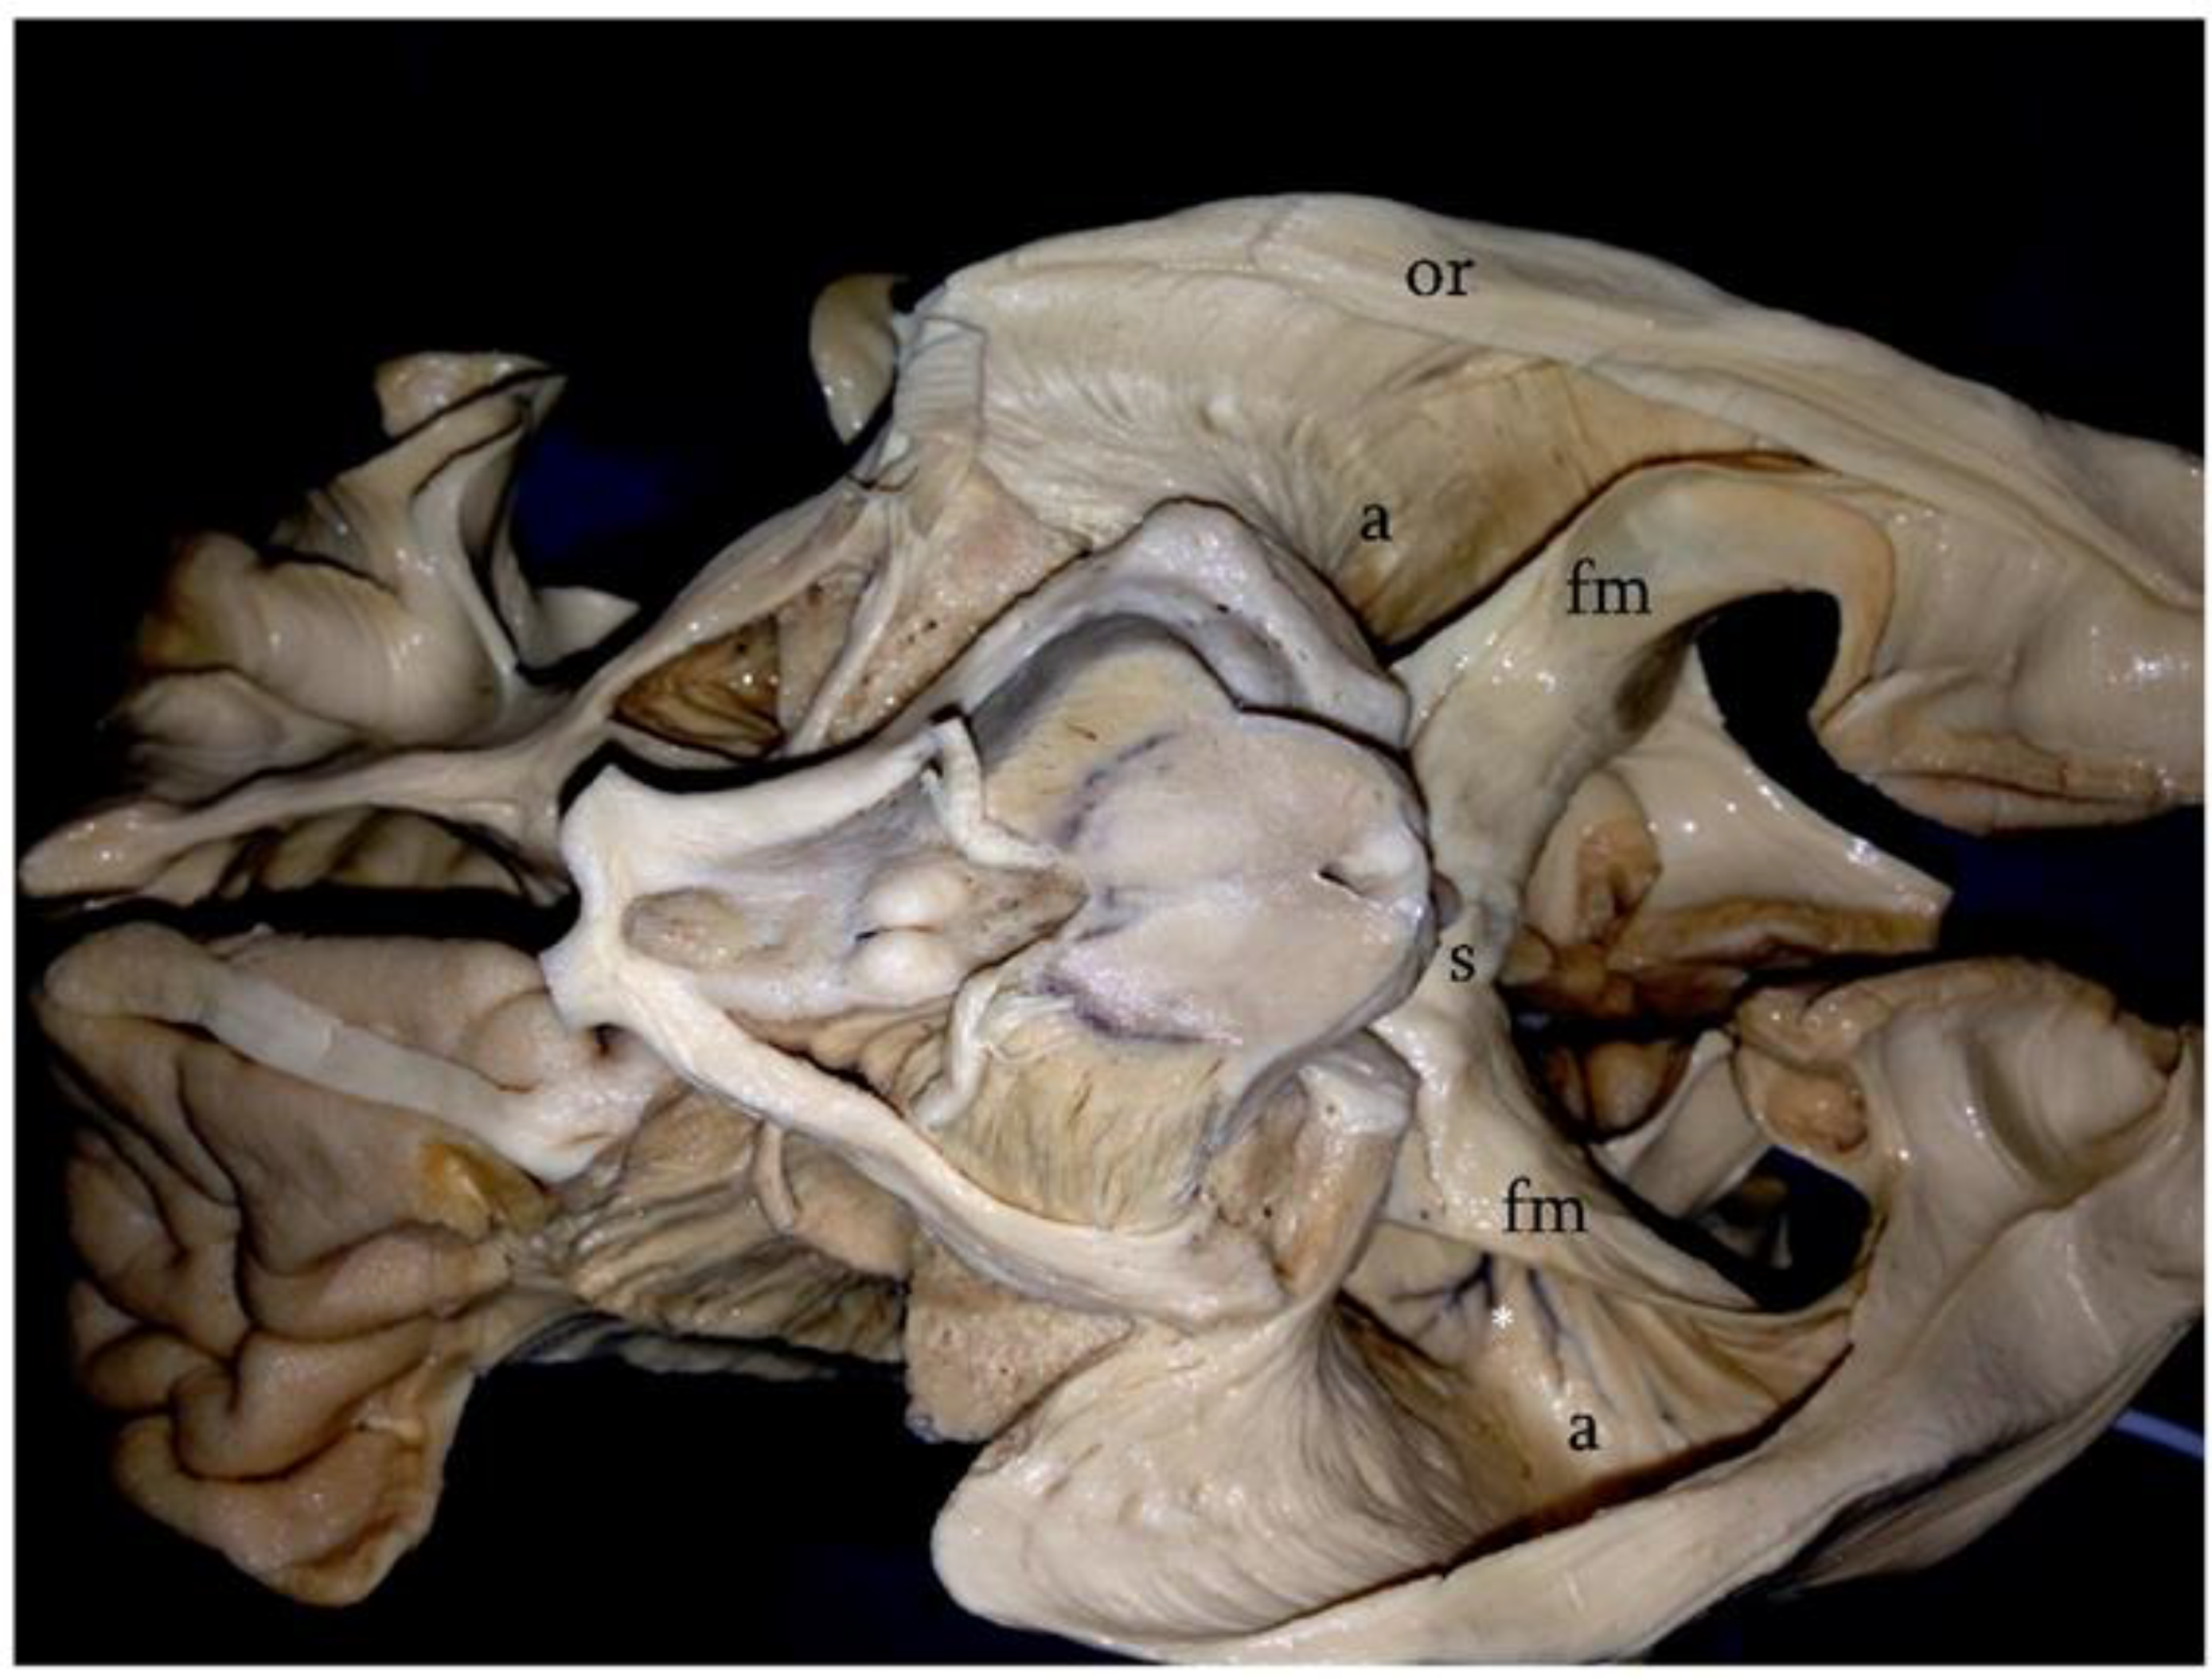

Figure 1. Klingler’s technique; basal surface of the cerebral hemispheres after the removal of the fusiform gyrus and inferior longitudinal fasciculus. In this photograph, the relationships between the atrial cavity (a) and the white matter fibers of the region can be observed. The lateral wall of the atrium is entirely covered by the optic radiations (or). Medially, the splenial fibers (s) form the forceps major (fm). On the left side, note the ependymal veins identifying the atrial cavity (asterisk).

Surgical removal of tumors of the atrium is a challenge, even to the most seasoned neurosurgeons. The issues are related not only to the deep location of this portion of the lateral ventricles but also to the vascularization of lesions of this area and to their complex three-dimensional relationships with the highly functional white matter fibers of the region [1,2,3]. In fact, the lateral wall of the atrium is entirely covered by a complicated system of fibers known as the sagittal stratum, which includes the optic radiations and some contingents of parietopontine and occipitopontine fibers. The basal surface is covered by the inferior longitudinal fasciculus, whereas white matter fibers related to the medial surface are the cingulum and the forceps major [4,5,6,7,8,9] (Figure 1). Given the functional importance of these structures and the often-benign nature of the lesions involving this area, an efficient approach to the atrium should be able to combine a total resection with respect to the anatomo-functional integrity of the white matter fibers [10]. Bearing this concept in mind, several surgical approaches to the atrium have been proposed [4]. The ipsilateral interhemispheric transprecuneus (IITA) approach satisfies these requisites. In this work, we present a clinical series of patients affected by tumors of the atrium that were approached through this elegant and complicated route. A detailed description of the technical aspects of the approach and a comparison with the possible alternatives is also given.

Moreover, the atrium is entirely encircled by a highly functional system of white matter fibers that should be preserved during the surgical removal of tumors of this area. The main systems of fibers encountered while approaching the atrium are the optic radiation covering its lateral surface, the inferior longitudinal fasciculus extending along its base, and the splenial fibers together with the cingulum on the medial side [12]. All these systems of fibers play important and vital neurological functions. Moreover, in dominant hemispheres, the lateral wall of the atrium is in a close relationship with the system of fibers connecting the language areas [13,14].